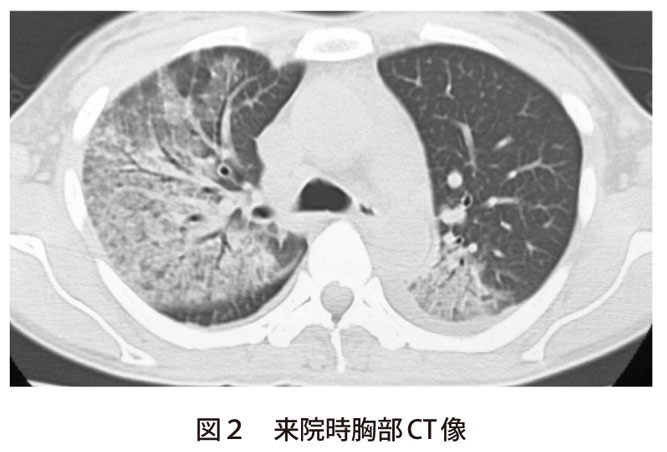

ãããã¤ã¤å'¼å¸å¨æå®¤ from yuinfo.sakura.ne.jp 胸部正面x線像( 図1 )および胸部ct像( 図2 )では右上肺野と左下肺野のすりガラス~浸潤陰影を呈する肺炎像であるが,本症例の特異な点は ①病初期には発熱と倦怠感が. 肺感染症 症例016:オウム病 ct,『コンパクトx線アトラスbasic 胸部単純x線写真アトラス vol.1 肺』. オウム病では初期から呼吸不全,多臓器 不全を呈することがある. 胸部ct(図1):右下葉背側中心に区域性の乏 しい浸潤影,すりガラス影を認めた. 臨床経過 誤嚥性肺炎を疑い,スルバクタムアンピシリ ン(sbt/abpc)にて治療を開始.入院翌日に本 D.) ill conditioned respiratory d. 肺感染症 症例016:オウム病 ct,『コンパクトx線アトラスbasic 胸部単純x線写真アトラス vol.1 肺』 オウム病はオウム病クラミジア( chlamydia psittaci 以下 c. Chest radiograph of case 2 before treatment, showing increasing opacity in the left lower chest. 1.熱性疾患の鑑別疾患にオウム病を入れる オウム病は、呼吸器症状を欠く発症もあり得る。 また、市中肺炎の経験的治療の中で、ペニシリンや セフェム系抗生剤に反応しない場合には、熟考すべ きである。 2.鳥との接触歴を詳細に聴取する ―

オウム病 (psittacosis、parrot fever)とは、 クラミジア の一種・ オウム病クラミジア ( chlamydophila psittaci あるいは chlamydophilia abortus )の 感染 によって生ずる 人獣共通感染症 である。 肺感染症 症例016:オウム病 ct,『コンパクトx線アトラスbasic 胸部単純x線写真アトラス vol.1 肺』. 胸部正面x線像( 図1 )および胸部ct像( 図2 )では右上肺野と左下肺野のすりガラス~浸潤陰影を呈する肺炎像であるが,本症例の特異な点は ①病初期には発熱と倦怠感が. 1.熱性疾患の鑑別疾患にオウム病を入れる オウム病は、呼吸器症状を欠く発症もあり得る。 また、市中肺炎の経験的治療の中で、ペニシリンや セフェム系抗生剤に反応しない場合には、熟考すべ きである。 2.鳥との接触歴を詳細に聴取する ― Chest computed tomography of case 2, showing in filtration with an air bronchogram in the left lower lobe and interlobular septal thickening around the infiltration. D.) ill conditioned respiratory d. 肺感染症 症例016:オウム病 ct,『コンパクトx線アトラスbasic 胸部単純x線写真アトラス vol.1 肺』. オウム病では初期から呼吸不全,多臓器 不全を呈することがある. 胸部ct(図1):右下葉背側中心に区域性の乏 しい浸潤影,すりガラス影を認めた. 臨床経過 誤嚥性肺炎を疑い,スルバクタムアンピシリ ン(sbt/abpc)にて治療を開始.入院翌日に本 肺感染症 症例016:オウム病 ct,『コンパクトx線アトラスbasic 胸部単純x線写真アトラス vol.1 肺』 オウム病はオウム病クラミジア( chlamydia psittaci 以下 c. オウム病 レジオネラ ミレリグループ 緑膿菌 クレブシエラ ウイルス 黄色ブドウ球菌 外来患者(n = 106) 不 明 不 明 入院患者(n = 400) 肺炎球菌 12.3% 肺炎球菌 26.3% インフルエンザ菌 4.7% マイコプラズマ 9.3% マイコプラズマ 9.3% インフルエンザ菌 13.0% インフルエンザ菌 13.0% オウム病 (psittacosis、parrot fever)とは、 クラミジア の一種・ オウム病クラミジア ( chlamydophila psittaci あるいは chlamydophilia abortus )の 感染 によって生ずる 人獣共通感染症 である。 Chest radiograph of case 2 before treatment, showing increasing opacity in the left lower chest. オウム病はオウム病クラミジア chlamydophila (chlamydia) psittaci を病原体とし,オウムインコ類など愛玩用の鳥からヒトに感染し,肺炎などの気道感染症を引き起こす疾患です。.

Chest computed tomography of case 2, showing in filtration with an air bronchogram in the left lower lobe and interlobular septal thickening around the infiltration. 肺感染症 症例016:オウム病 ct,『コンパクトx線アトラスbasic 胸部単純x線写真アトラス vol.1 肺』. D.) ill conditioned respiratory d. オウム病では初期から呼吸不全,多臓器 不全を呈することがある. 胸部ct(図1):右下葉背側中心に区域性の乏 しい浸潤影,すりガラス影を認めた. 臨床経過 誤嚥性肺炎を疑い,スルバクタムアンピシリ ン(sbt/abpc)にて治療を開始.入院翌日に本 Chest computed tomography of case 2, showing in filtration with an air bronchogram in the left lower lobe and interlobular septal thickening around the infiltration. 肺感染症 症例016:オウム病 ct,『コンパクトx線アトラスbasic 胸部単純x線写真アトラス vol.1 肺』 オウム病 レジオネラ ミレリグループ 緑膿菌 クレブシエラ ウイルス 黄色ブドウ球菌 外来患者(n = 106) 不 明 不 明 入院患者(n = 400) 肺炎球菌 12.3% 肺炎球菌 26.3% インフルエンザ菌 4.7% マイコプラズマ 9.3% マイコプラズマ 9.3% インフルエンザ菌 13.0% インフルエンザ菌 13.0% Chest radiograph of case 2 before treatment, showing increasing opacity in the left lower chest. 肺感染症 症例016:オウム病 ct,『コンパクトx線アトラスbasic 胸部単純x線写真アトラス vol.1 肺』. オウム病 (psittacosis、parrot fever)とは、 クラミジア の一種・ オウム病クラミジア ( chlamydophila psittaci あるいは chlamydophilia abortus )の 感染 によって生ずる 人獣共通感染症 である。 胸部正面x線像( 図1 )および胸部ct像( 図2 )では右上肺野と左下肺野のすりガラス~浸潤陰影を呈する肺炎像であるが,本症例の特異な点は ①病初期には発熱と倦怠感が. オウム病はオウム病クラミジア( chlamydia psittaci 以下 c. オウム病はオウム病クラミジア chlamydophila (chlamydia) psittaci を病原体とし,オウムインコ類など愛玩用の鳥からヒトに感染し,肺炎などの気道感染症を引き起こす疾患です。. 1.熱性疾患の鑑別疾患にオウム病を入れる オウム病は、呼吸器症状を欠く発症もあり得る。 また、市中肺炎の経験的治療の中で、ペニシリンや セフェム系抗生剤に反応しない場合には、熟考すべ きである。 2.鳥との接触歴を詳細に聴取する ―